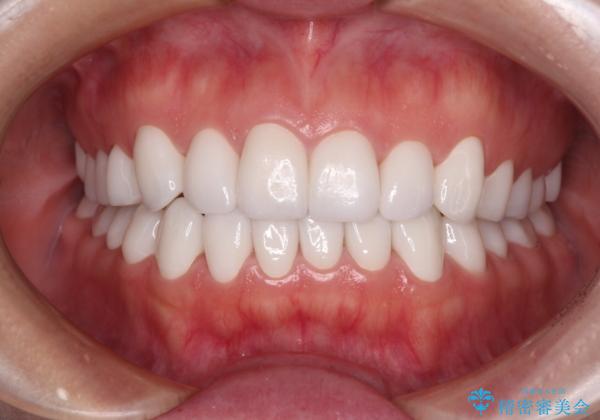

変色している歯をとにかく白く 全顎セラミック治療

当初は奥歯のみの治療をご希望でしたが、話を進めていくうちに、軽度ではあるものの、幼少期の薬の影響で歯が変色していることがコンプレックスであるということが分かりました。

長年歯の色が塞ぎ込んでいた部分があるとのことで、これを機会に全ての歯を真っ白にするために、オールセラミッククラウンにて補綴治療を行うこととしました。

より白さが目立つように、自然な仕上がりではなく、作り物の雰囲気があるフルジルコニアクラウンにて補綴治療を行いました。